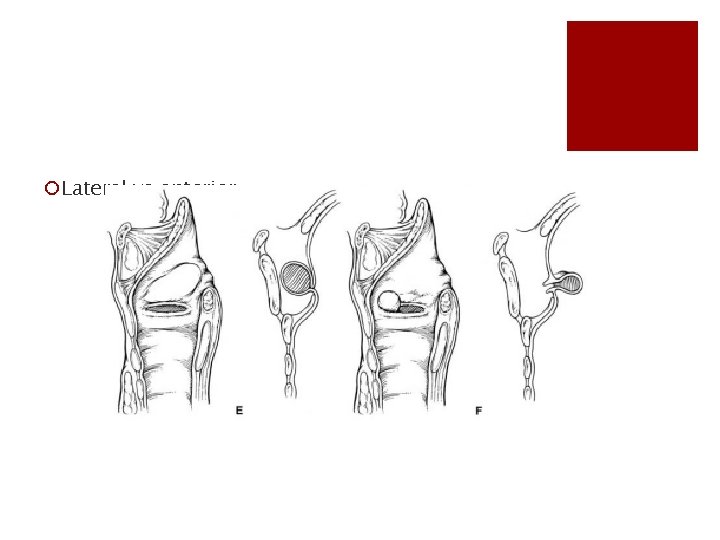

¡Lateral vs anterior

¡ A, Normal larynx B, internal laryngocele C, external laryngocele D, combined laryngocele E, lateral saccular cyst F, anterior saccular cyst